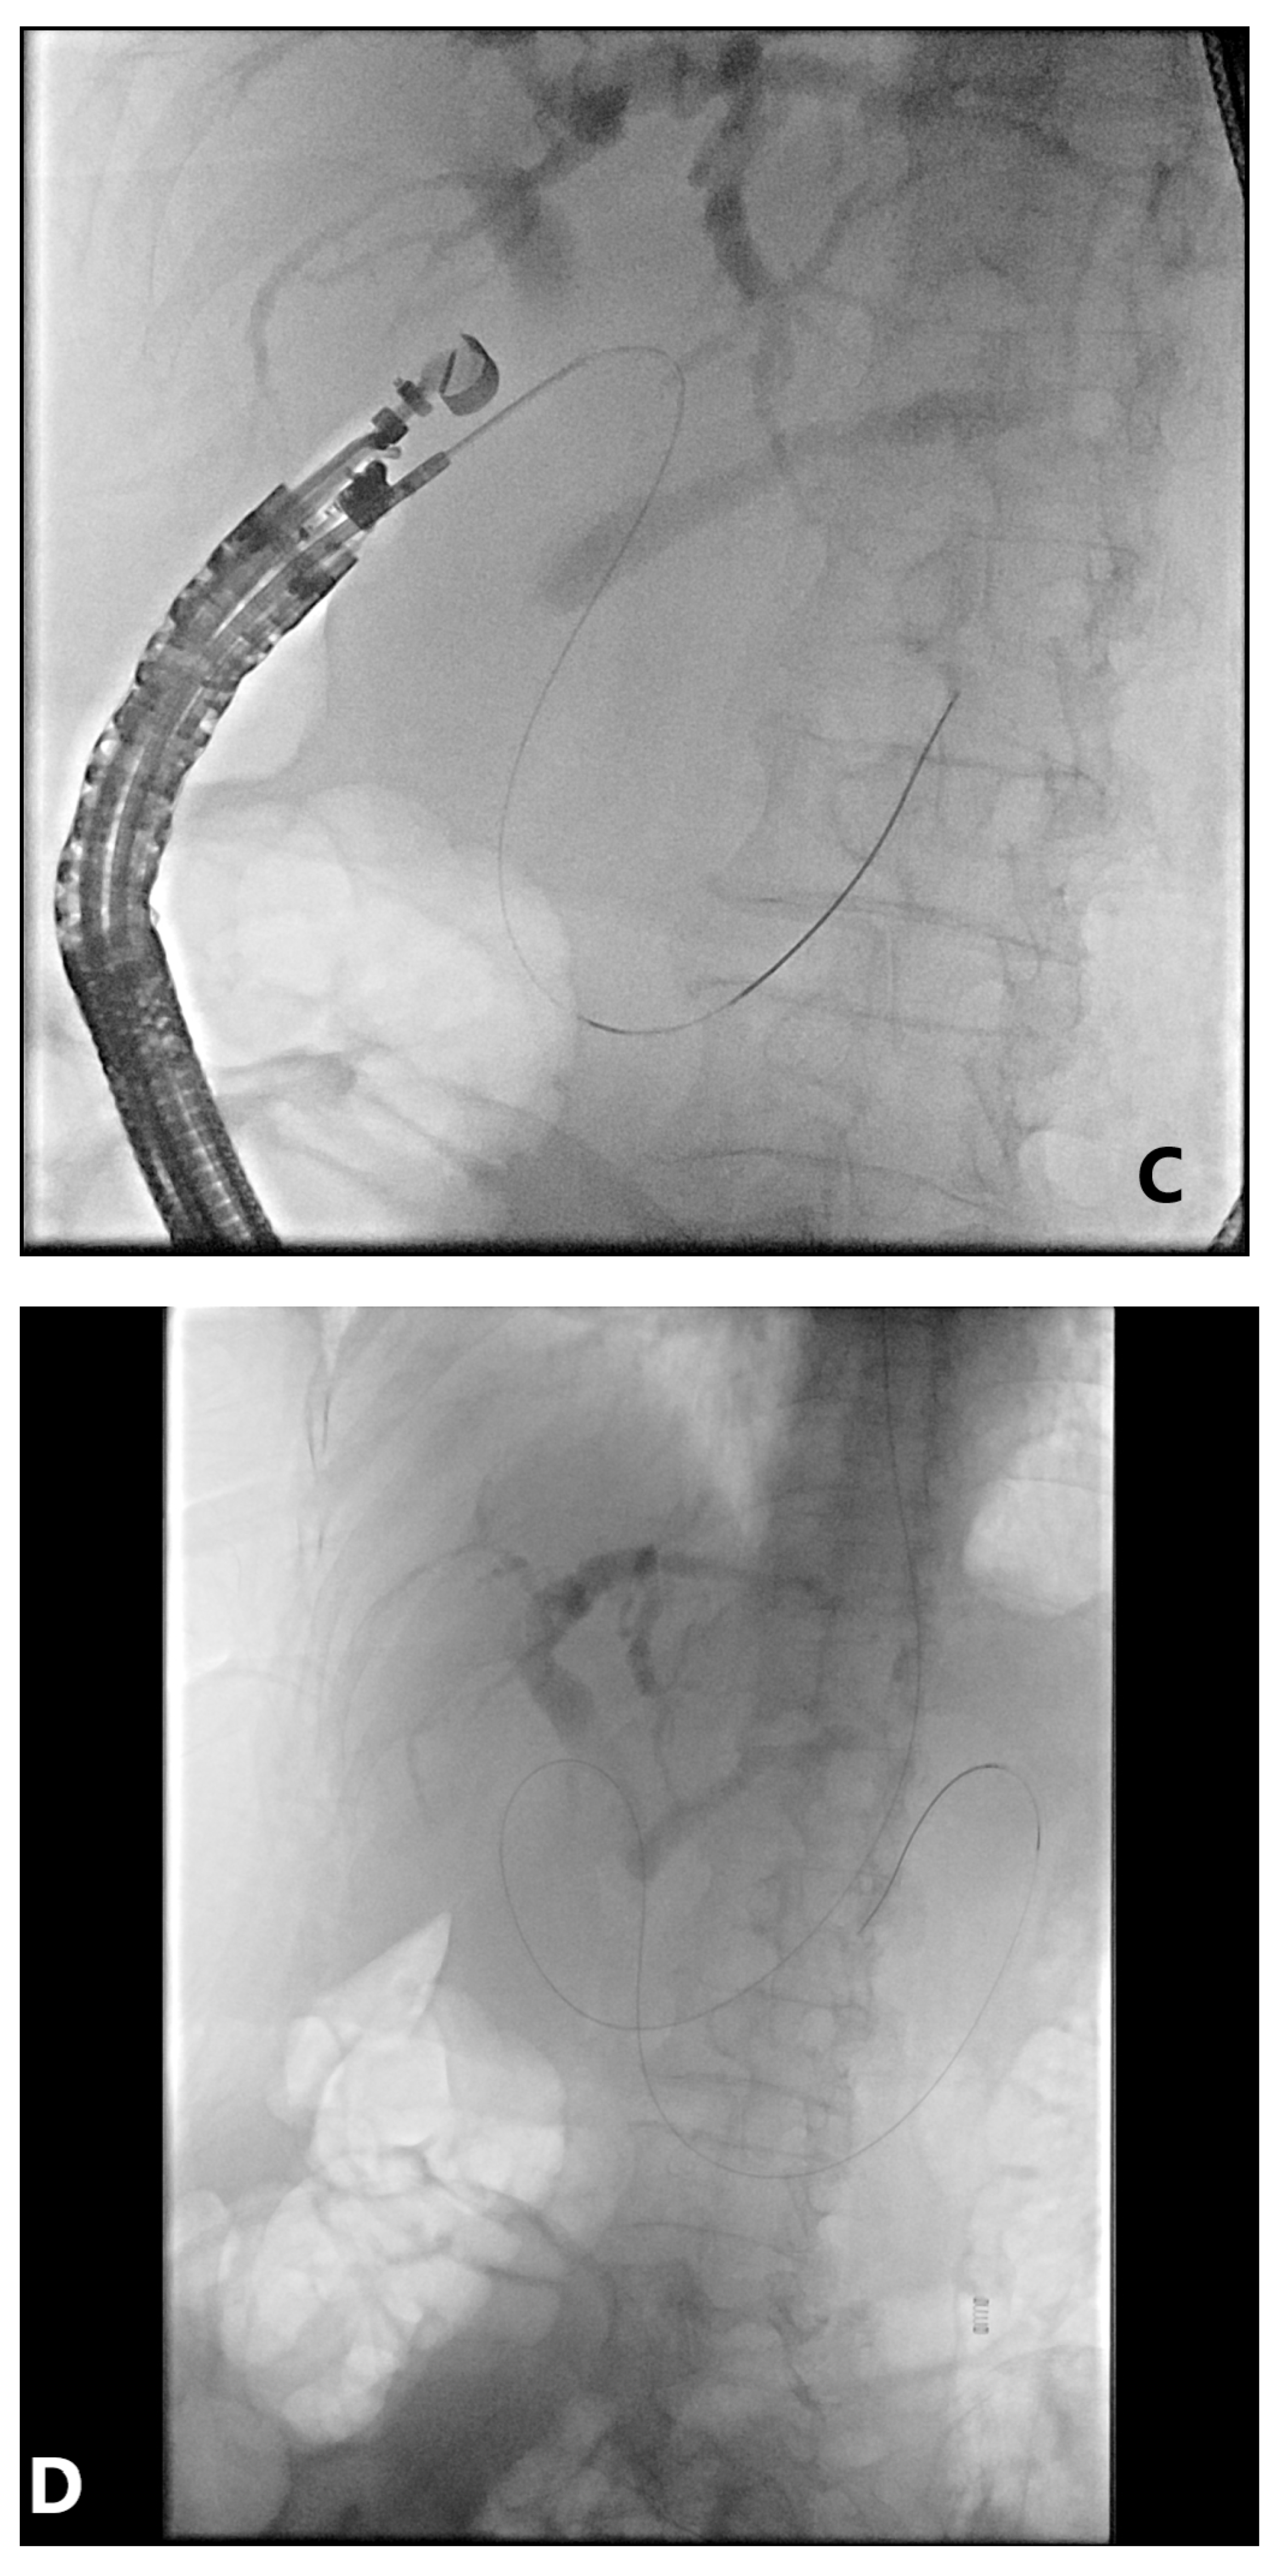

4. EUS-Guided Rendezvous (EUS-RV) Technique

4.1. Advantages

4.2. Disadvantages